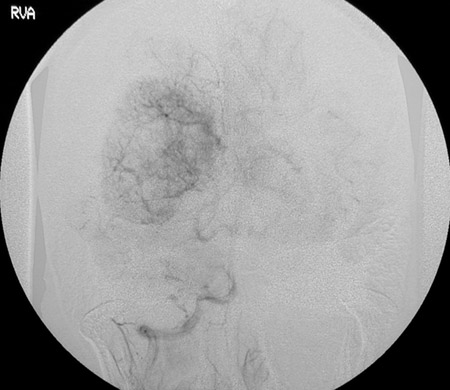

This cerebral angiogram with contrast injected into the right vertebral artery reveals a "blush" of contrast within the intraventricular meningioma seen in the prior MRI scan. The view above is earlier in the sequence than the view below.